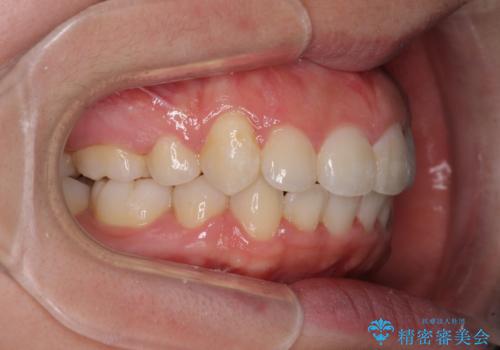

著しい叢生と顎骨のズレ ワイヤー装置による抜歯矯正

アンカーなどをうまく使用して、3年の期間を要してきれいに仕上げることができました。